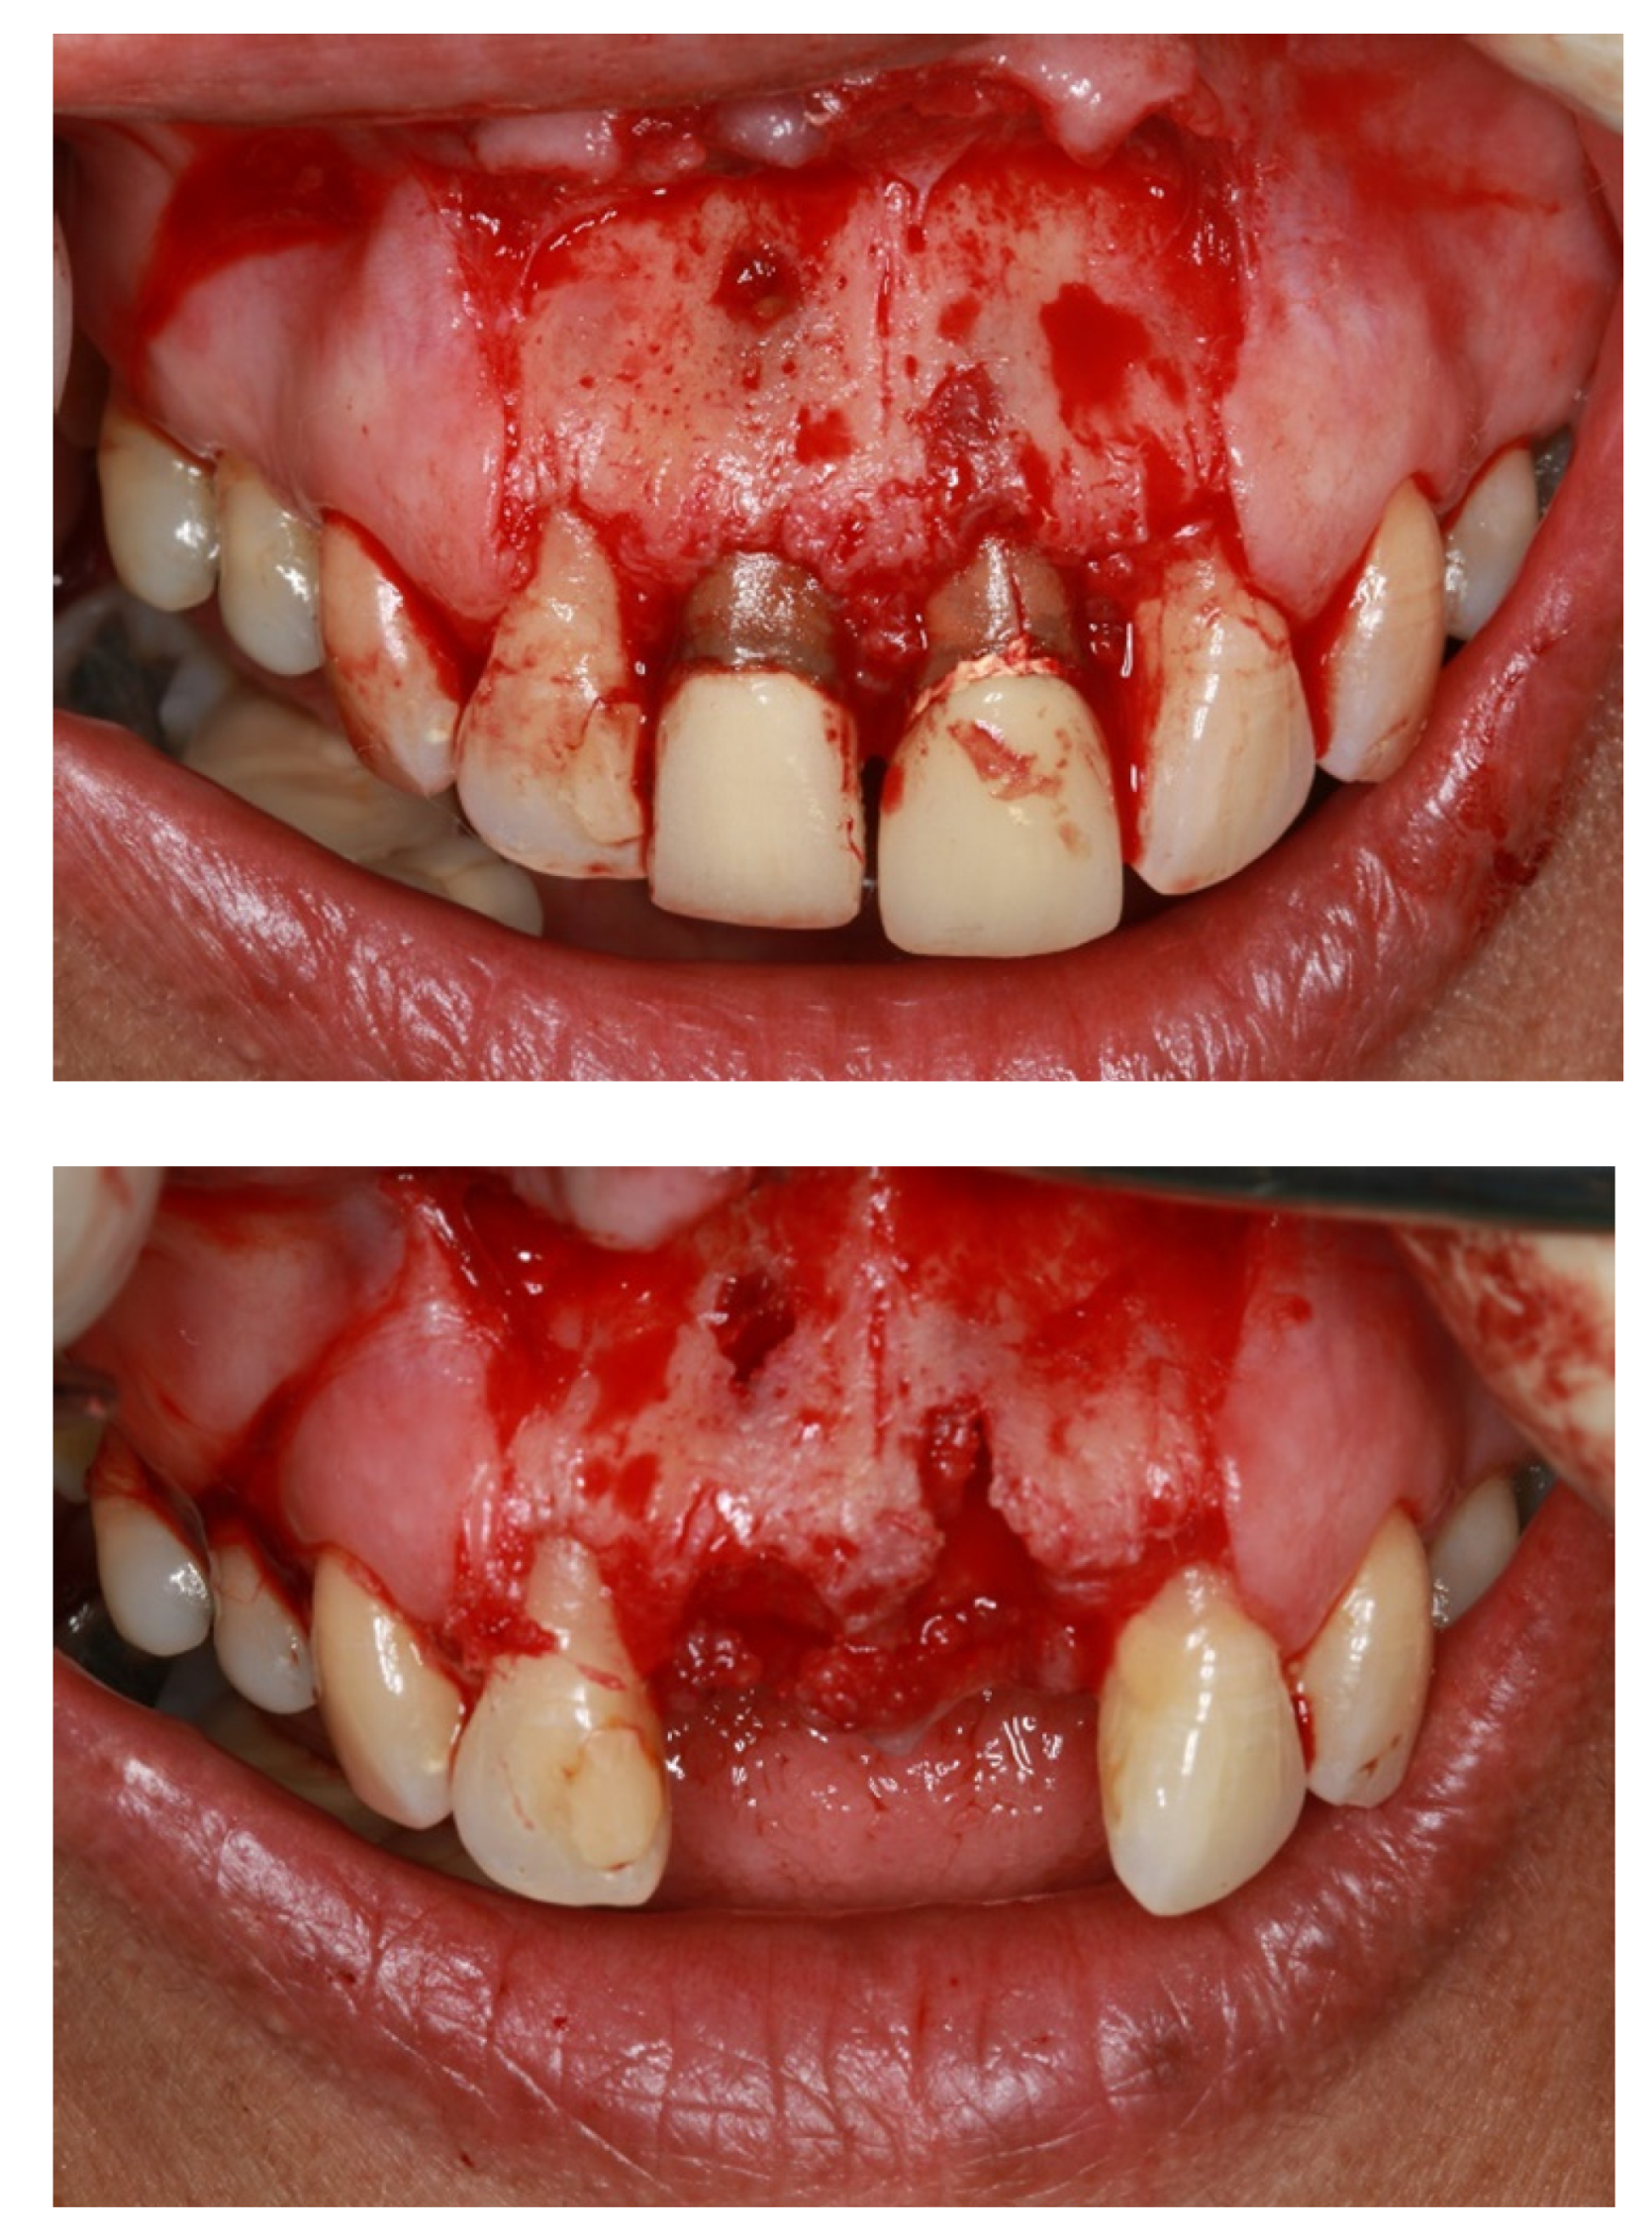

- Alauddin, M.S.; Ramli, H. Management of Membrane Exposure Utilizing Concentrated Growth Factor (CFG) in Guided Bone Regeneration: A Clinical Report. Open Dent. J. 2020, 14, 763–768. [Google Scholar] [CrossRef]